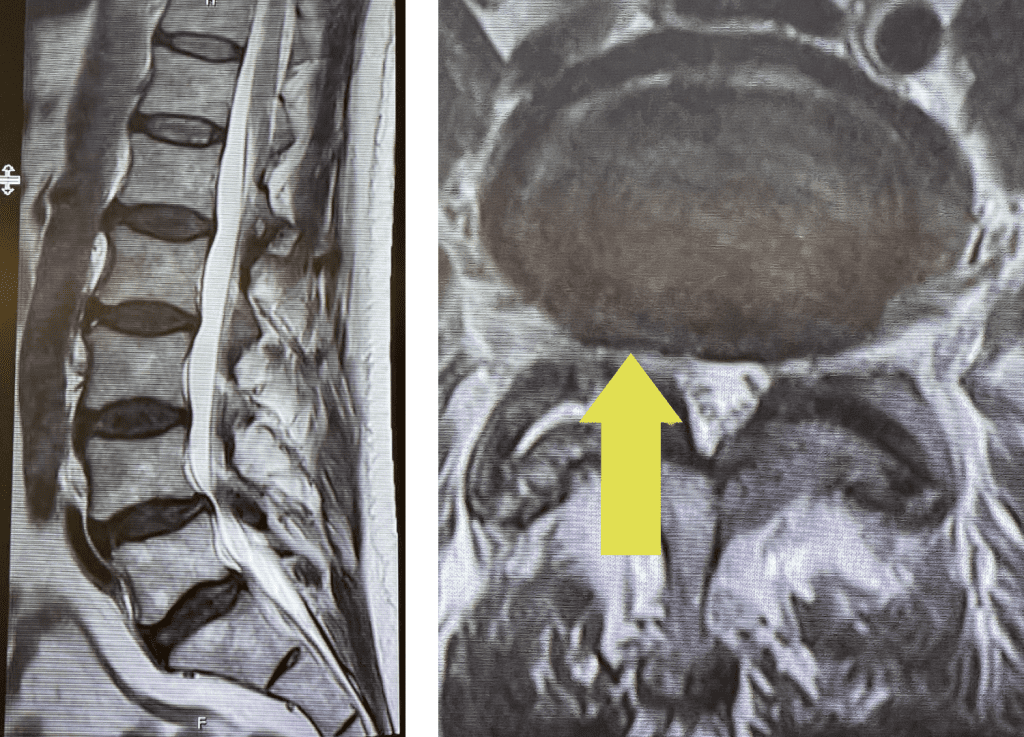

Fig 2: Intraoperative photo showing the thecal sac (arrow)completely decompressed after L3-5 laminectomy. Note the L5 nerve root very well decompressed (asterix)

During the surgery we perform what is called a decompressive laminectomy. Because he had the slip at L4-5 he required a fusion in addition. We elected to use screws with bone graft. People wonder what an actual laminectomy is. A laminectomy is a procedure to remove or “ectomy” the back ring of bone of the spinal segment .You literally bite it away with our special instruments. This bone is called the lamina. You do not need the lamina to live, like an appendix. There are gaps between each lamina segment going up the spine to begin with and there is a tremendous amount of tissue including muscle so one is protected, and it is ok to do this. You need to do the laminectomy to shave away the material that is both hard and soft that is compressing the sac of nerves. Your goal in the surgery is to make the sac nice and round again with a normal diameter. Since in the lumbar spine there is no spinal cord you are dealing with the peripheral nervous system not the central nervous system like the brain and spinal cord. A sac of nerves floating in fluid is a protected system, like a baby in amniotic fluid. At the same time you must not only remove the pressure on the sac, but also you must shave away the pressure on the nerve roots as well, which is called a foraminotomy (Fig 2). The nice thing about a fusion is you can be aggressive in the amount of decompression and joint removal you can do because you are fixing chronic as well as iatrogenic acute instability.